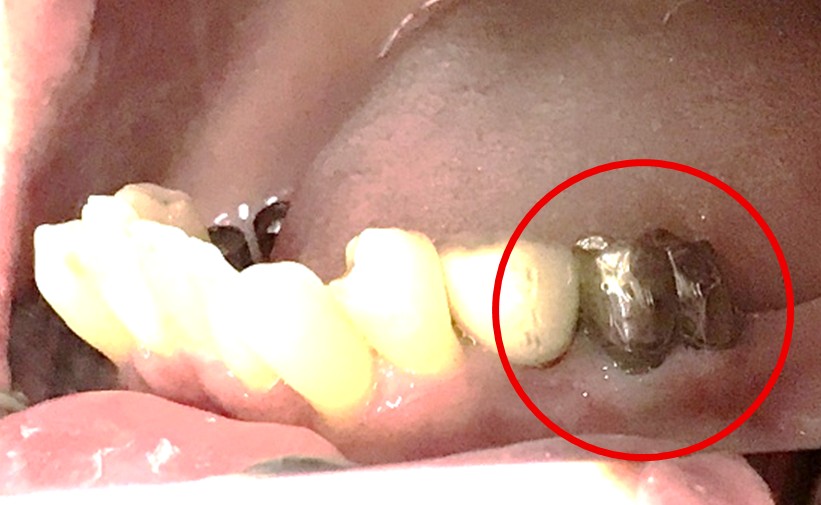

男性 Mさん 50代 (オールセラミック冠)

主訴

右上奥歯が、冷たいものにしみる。

治療内容

歯髄(神経および血管)まで到達する大きな虫歯でしたので、抜髄(歯髄を取り除く)をし、ファイバーコアをいれ、オールセラミック冠を被せました。

所感

現在、保険治療において、限定的ではありますが、大臼歯にも白い被せ物(プラスチック冠)ができるようになりました。しかし、実感としてプラスチック冠は、

- すり減りやすい。割れることがある。

- バイオフィルム(細菌およびそれから産生される副産物の塊)が付着しやすいので、歯周病および2次カリエス(被せ物と自分の歯の境目から再度虫歯になる)になるリスクが高い。

- 変色する。

という点を感じます。白い被せ物が保険の治療でできるという理由で、安易にプラスチック冠を選択し、割れたりすり減ったり、変色したらもう一度被せなおせばいいと考えるのであれば、一度立ち止まって考えてみてください。歯の量は、治療するたびに薄く少なくなり、歯根破折のリスクが高まります。もし大きな虫歯になってしまったら、最高レベルの根管治療をし、最良の被せ物であるオールセラミック冠を被せ、定期的にお口の中のクリーニングをし、同じ歯を2度と治療しないことが、歯を長持ちさせる最良の方法だと考えます。

オールセラミック冠(失活歯):¥104,500(税込)

Before

劣化したプラスチック冠

After